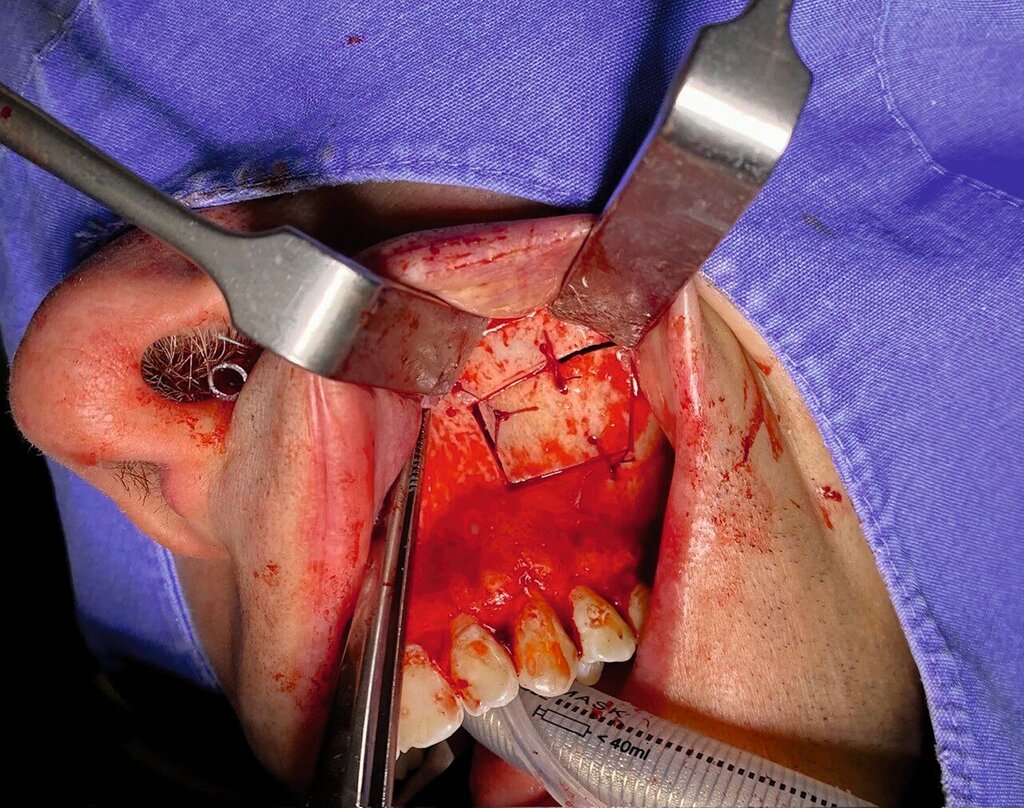

Die Therapie erfolgte in ambulanter Vollnarkose mittels Lindorf-Deckel-Technik. Nach marginaler Schnittführung und Darstellung der Kieferhöhlenvorderwand wurde mittels Piezosurgery ein knöcherner Deckel präpariert und der Sinus eröffnet (Abbildung 3). Es zeigten sich eine große Menge bröckeliges, schwarz verfärbtes Material sowie eine entzündlich veränderte Schleimhaut (Abbildung 4).

Zudem wurde ein Zahnkronenfragment geborgen (Abbildung 7). Die Kieferhöhle wurde unter Erhalt der auskleidenden Schleimhaut vollständig gereinigt und mit physiologischer Kochsalzlösung gespült. Zur postoperativen Spültherapie wurde transnasal ein Drainageröhrchen durch das Ostium naturale eingelegt (Abbildung 5). Auf ein Fenster zum unteren Nasengang wurde daher verzichtet. Der Knochendeckel wurde reponiert und mit resorbierbaren Nähten fixiert (Abbildung 6).